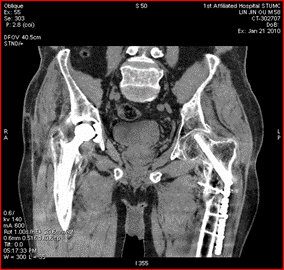

新技術(shù)介紹四:高心率冠脈成像、高清成像

此例為心率83~88bpm,冠狀動脈成像優(yōu)異

寶石能譜CT突破了以往64排CT冠脈掃描時對心率的苛刻要求,增加了患者的接受度,簡化了冠脈CTA成像流程。

高清模式清晰顯示支架術(shù)后再發(fā)斑塊形成

高清模式突破了傳統(tǒng)CT對支架內(nèi)斑塊觀察的難點,能夠提供冠脈支架內(nèi)腔的高清圖像。